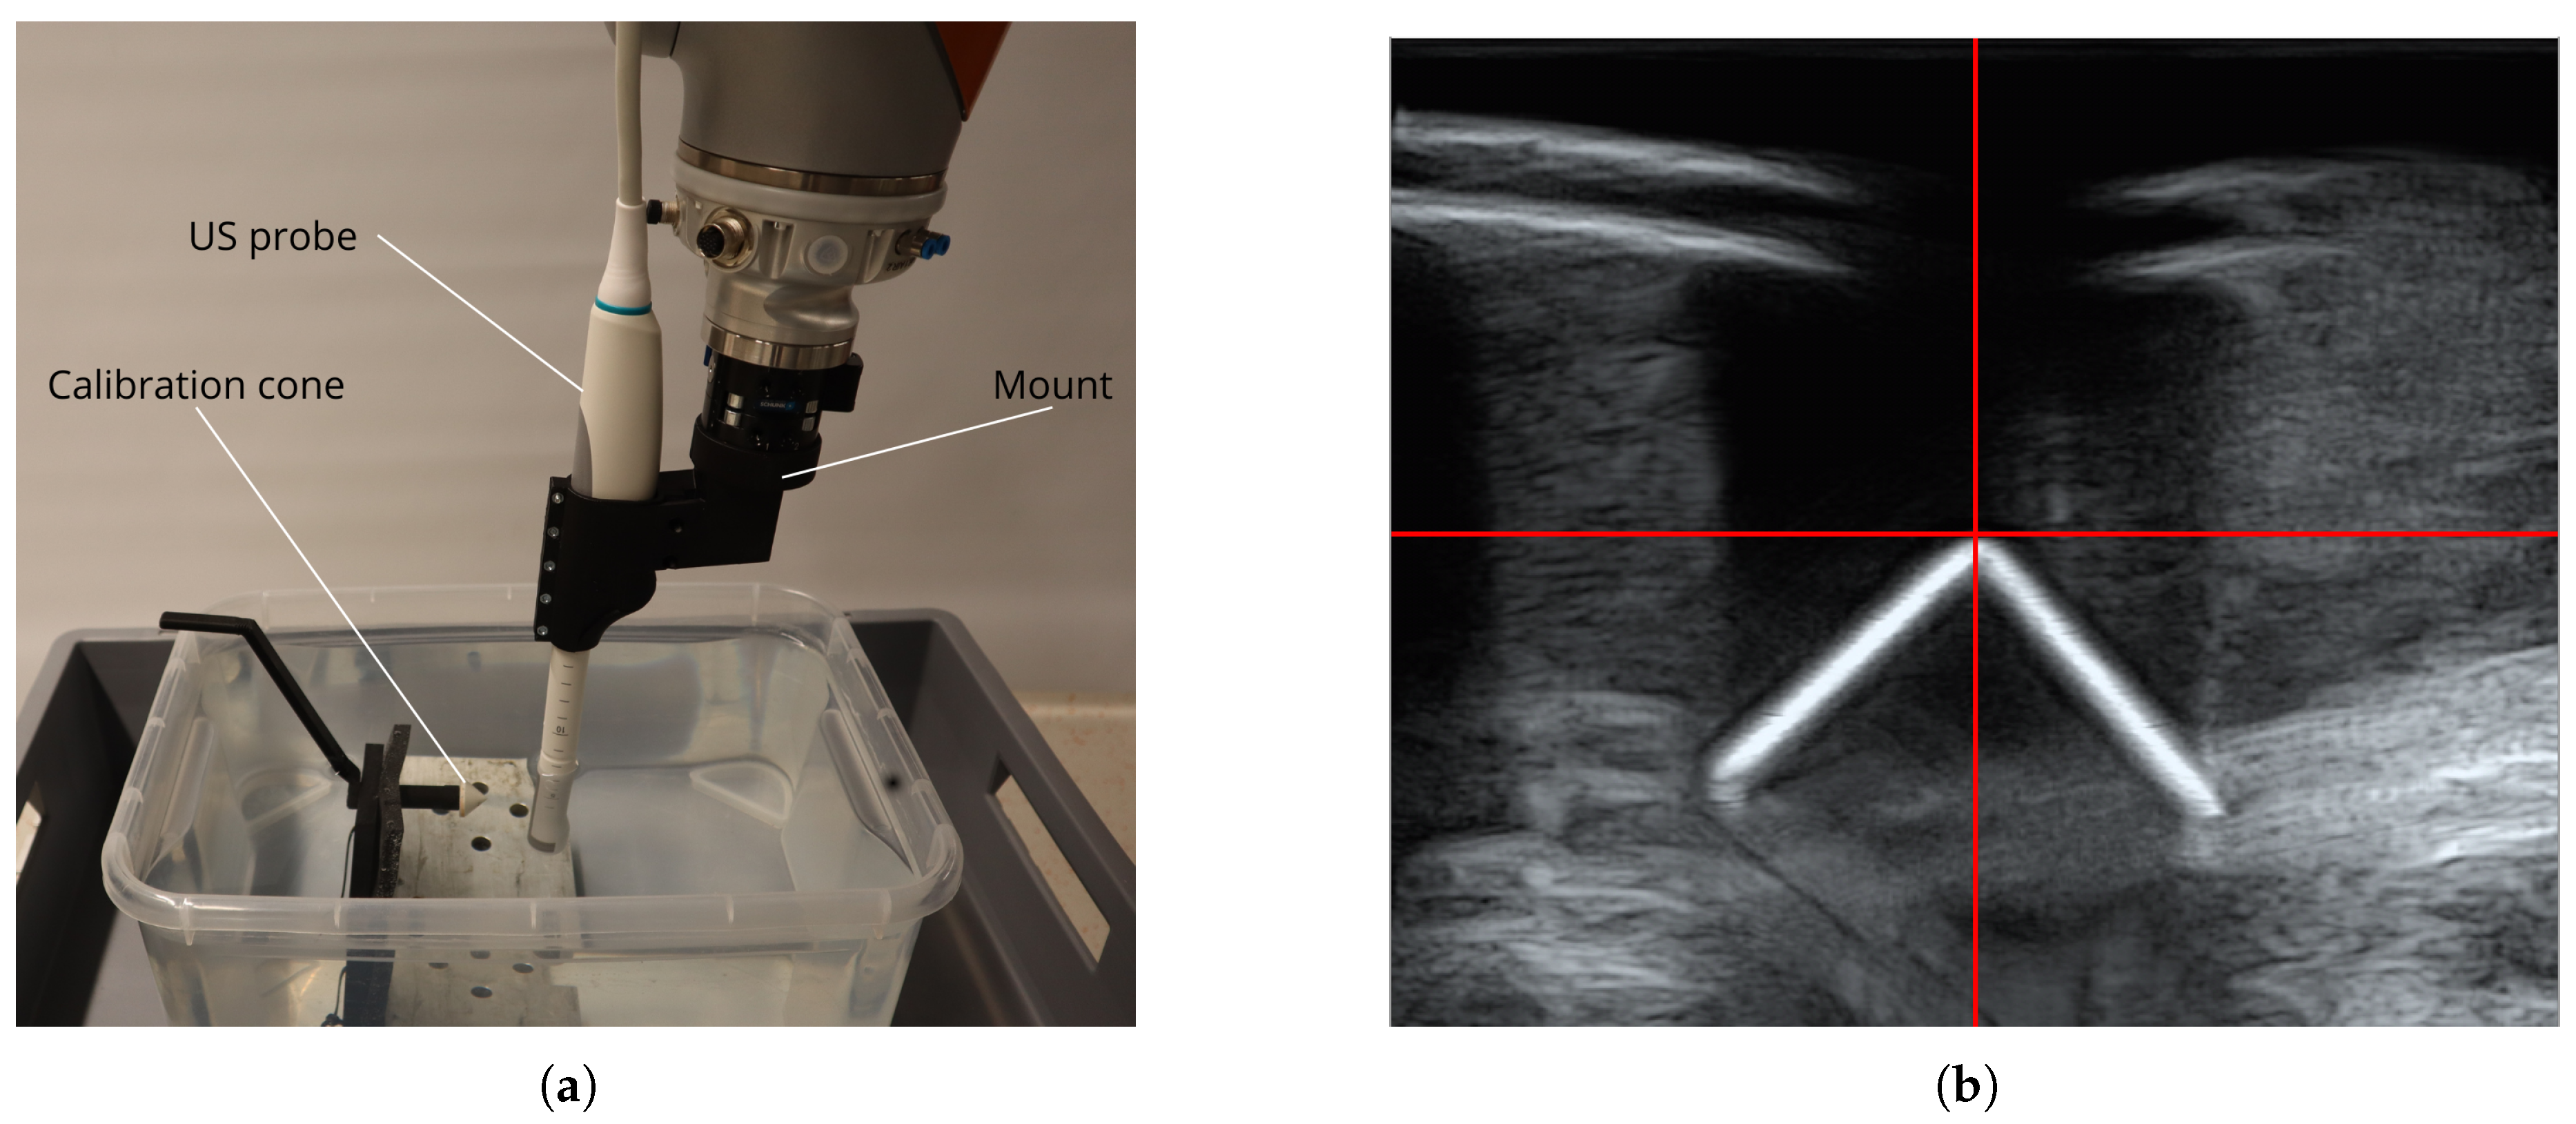

- Suligoj, F.; Heunis, C.M.; Sikorski, J.; Misra, S. RobUSt–An Autonomous Robotic Ultrasound System for Medical Imaging. IEEE Access 2021, 9, 67456–67465. [Google Scholar] [CrossRef]